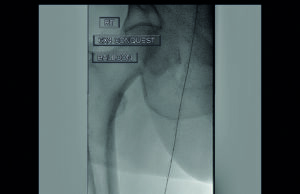

Radiation safety session seeks to address variability and improve access to...

“Variability is a source of inferior quality, poor outcomes and harm,” says Anil Hingorani, MD, vascular surgeon at New York University (NYU) Langone in...